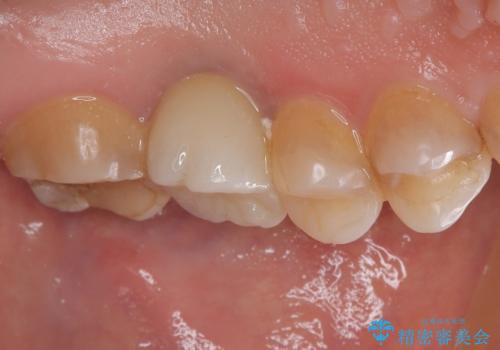

インプラント治療をきっかけに、銀歯を全てセラミックに替えていきました。

人の目を気にせずに、大きく口を開けて笑えるようになりました。